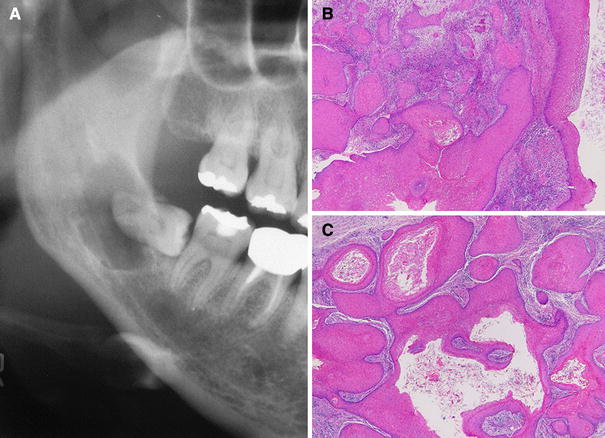

Cystic Squamous Odontogenic Tumor

During routine dental treatment, a well-defined, unilocular radiolucency enclosing the root of a horizontally impacted right lower third molar was found in a 46-year-old woman (Fig. 3a). A solid mass was excised along with the tooth. On microscopic examination, there were interconnected budding islands of bland squamous epithelium reminiscent of pseudoepitheliomatous hyperplasia, in addition to large cystic spaces containing desquamated keratin (Fig. 3b, c). The cyst lining had neither basal palisading nor corrugated parakeratin layer and immunostaining for Bcl-2 was negative. After a search of the relevant literature, the most likely diagnosis at this time was cystic squamous odontogenic tumor. A few tumor nests were found in the resection margins, but there has been no sign of recurrence in the ensuing 3 years.

Fig. 3

Cystic squamous odontogenic tumor. a Panoramic radiograph, b and c solid-cystic proliferation of mature squamous epithelium (Hematoxylin–Eosin, ×40)